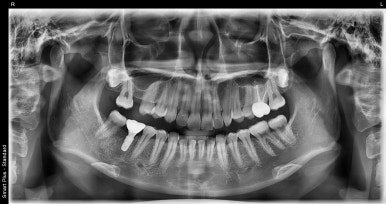

임플란트 픽스처 식립 후

20대 남성

2023-07-25

다행히 발치 당일에 임플란트 식립이 가능하다고 판단되어 오른쪽 위아래 사랑니와 함께

#47 치아를 발치하고 바로 임플란트를 식립할 수 있었습니다.

3개월 후 치아 역할을 해줄 보철물까지 올리기로 했는데요.

아마 올해 10월 쯤이면 환자분도 새로운 치아를 갖게 되실 것 같습니다 ^^